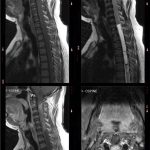

Neurosurgery and neuroradiology always go hand in hand. This little weekly activity is going to enhance the scan reading skills of our audience in an interactive way. Waiting for the answer for a week will keep the curiosity alive and will keep our target audience hooked to the website. It will prove to be a seamless share of knowledge and reading skills.

Dr. Saqib Kamran Bakhshi started the PANS Weekly Image Challenge in 2022, and his creativity and efforts made it a popular activity; engaging trainees and consultants in Pakistan and abroad.